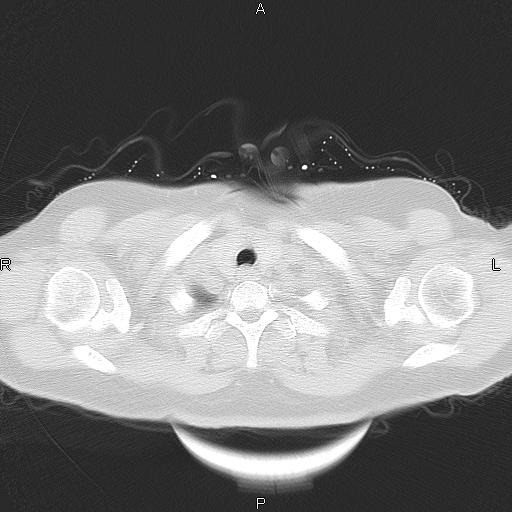

胸腺瘤

女、63Y 双眼睑下垂,早轻晚重。 胸腺瘤???

结果胸腺瘤